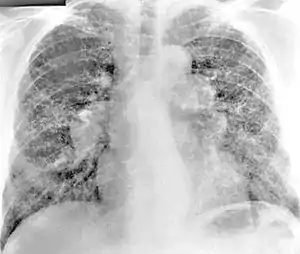

یافته های رادیوگرافی قفسه سینه از بریلیز غیر اختصاصی است. در اوایل بیماری ، یافته های رادیوگرافی طبیعی است. در مراحل بعدی فیبروز بینابینی ، بی نظمی پلور ، لنفادنوپاتی هیلار و کدورت های شیشه ای زمین گزارش شده است. یافته های مربوط به CT همچنین مختص بریلیزیس نیست. یافتن نتایج که در اسکن CT افراد مبتلا به بریلیوز رایج است ، شامل گره های پارانشیمی در مراحل اولیه است. یک مطالعه نشان داد که کدورت های شیشه ای زیر زمینی بیشتر در سی تی اسکن برلیوزیس در مقایسه با سارکوئیدوز مشاهده می شود. در مراحل بعدی لنفادنوپاتی هیلار ، فیبروز بینابینی ریوی و ضخیم شدن پلور مشاهده می شود [6][7].